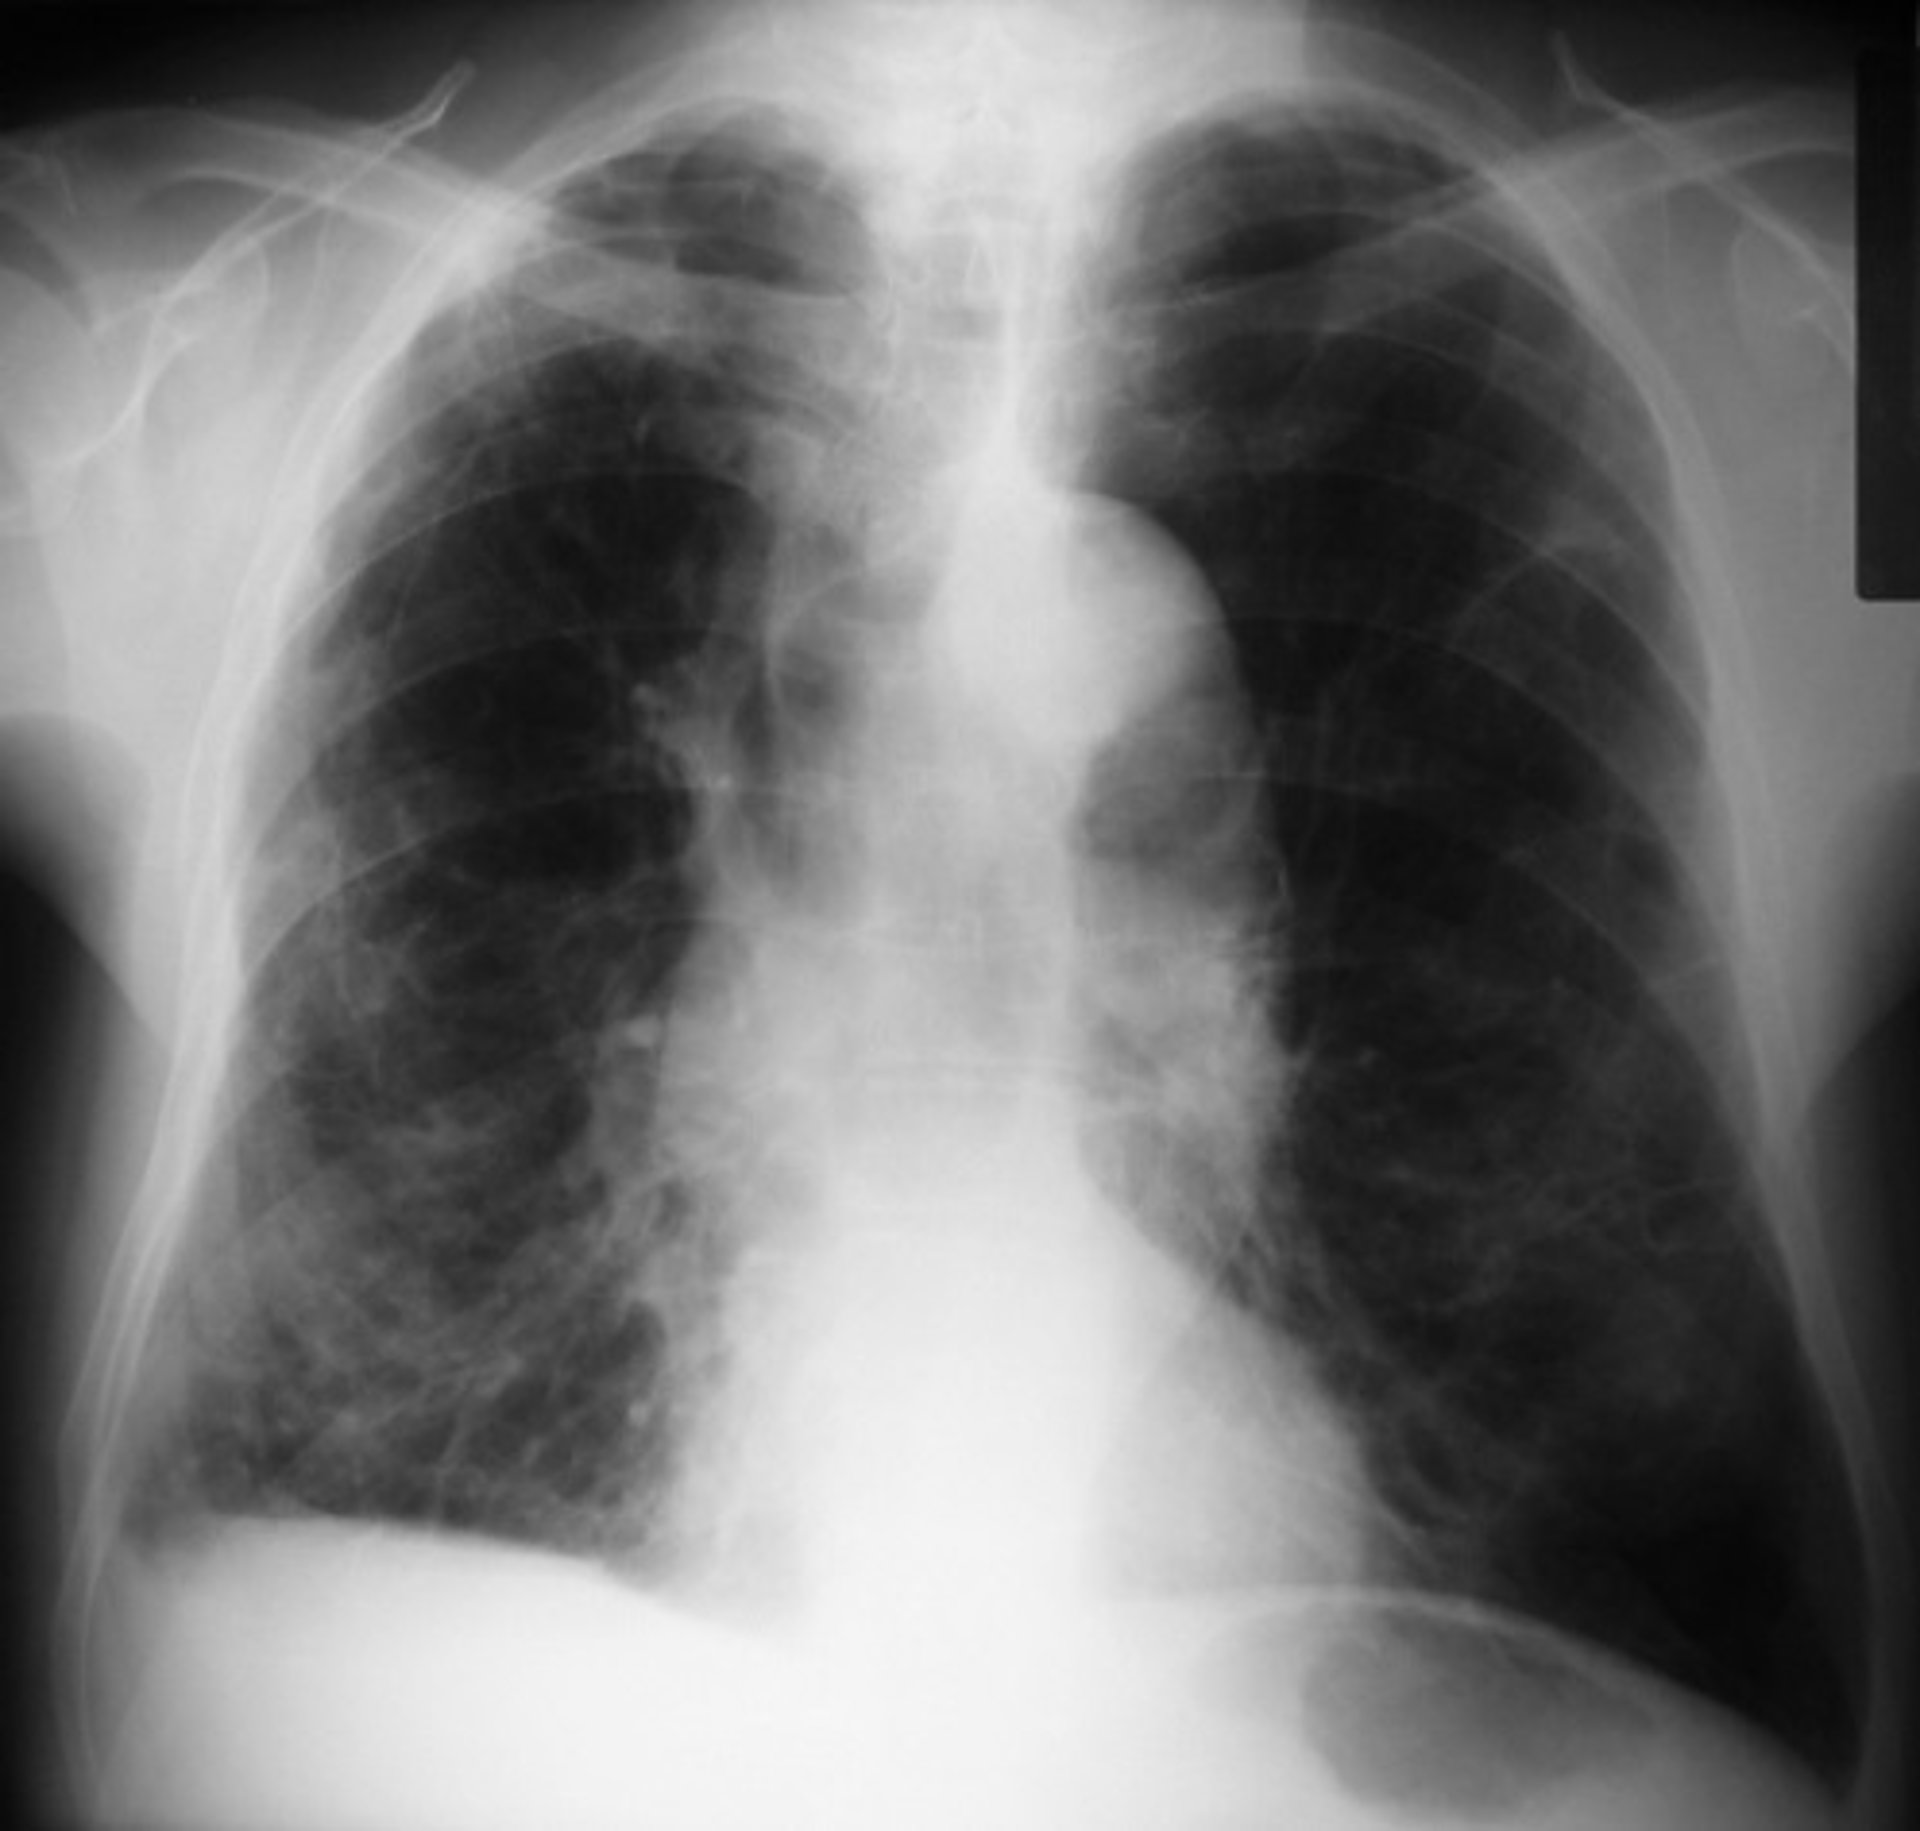

Una herramienta identifica qué pacientes con EPOC están en riesgo de muerte y complicaciones graves

Una nueva herramienta de decisión para ayudar a los médicos de urgencias a identificar a los pacientes con enfermedad pulmonar obstructiva crónica (EPOC) que tienen alto riesgo de complicaciones graves, incluida la muerte, funciona mejor que la práctica actual, según concluye un estudio de validación de la Escala de Riesgo de EPOC de Ottawa, Canadá, publicado en 'CMAJ'.

La enfermedad pulmonar obstructiva crónica, causada principalmente por fumar, es una afección común que afecta a la respiración y empeora con el tiempo. El estudio se realizó en seis hospitales de Ontario y Alberta con 1.415 pacientes de 50 años o más que se presentaron en los servicios de emergencia con brotes de EPOC.